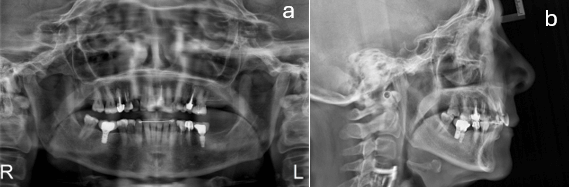

En la radiografía panorámica se observan contornos óseos regulares, las piezas dentarias 1.5, 1.4, 2.1, 3.4, 3.5 y 4.6 con endodoncia y coronas en unidades dentarias 1.5, 3.5 y 4.6 e imagen radiolúcida apical en la 1.5 de posible lesión previo al tratamiento de conducto, imagen radiopaca compatible con amalgamas en dientes 2.5, 2.6, 2.7 y 4.8. (fig. 3a)

En la telerradiografía lateral paciente Clase II esquelética, normodivergente, incisivos superiores retroinclinados e incisivos inferiores protruidos y proinclinados. (fig. 3b)

Figura 3.- Radiografías Iniciales

a) Panorámica b) Telerradiografía lateral c) Periapical total